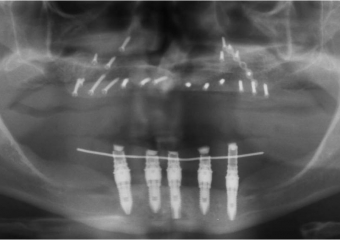

Raio X final